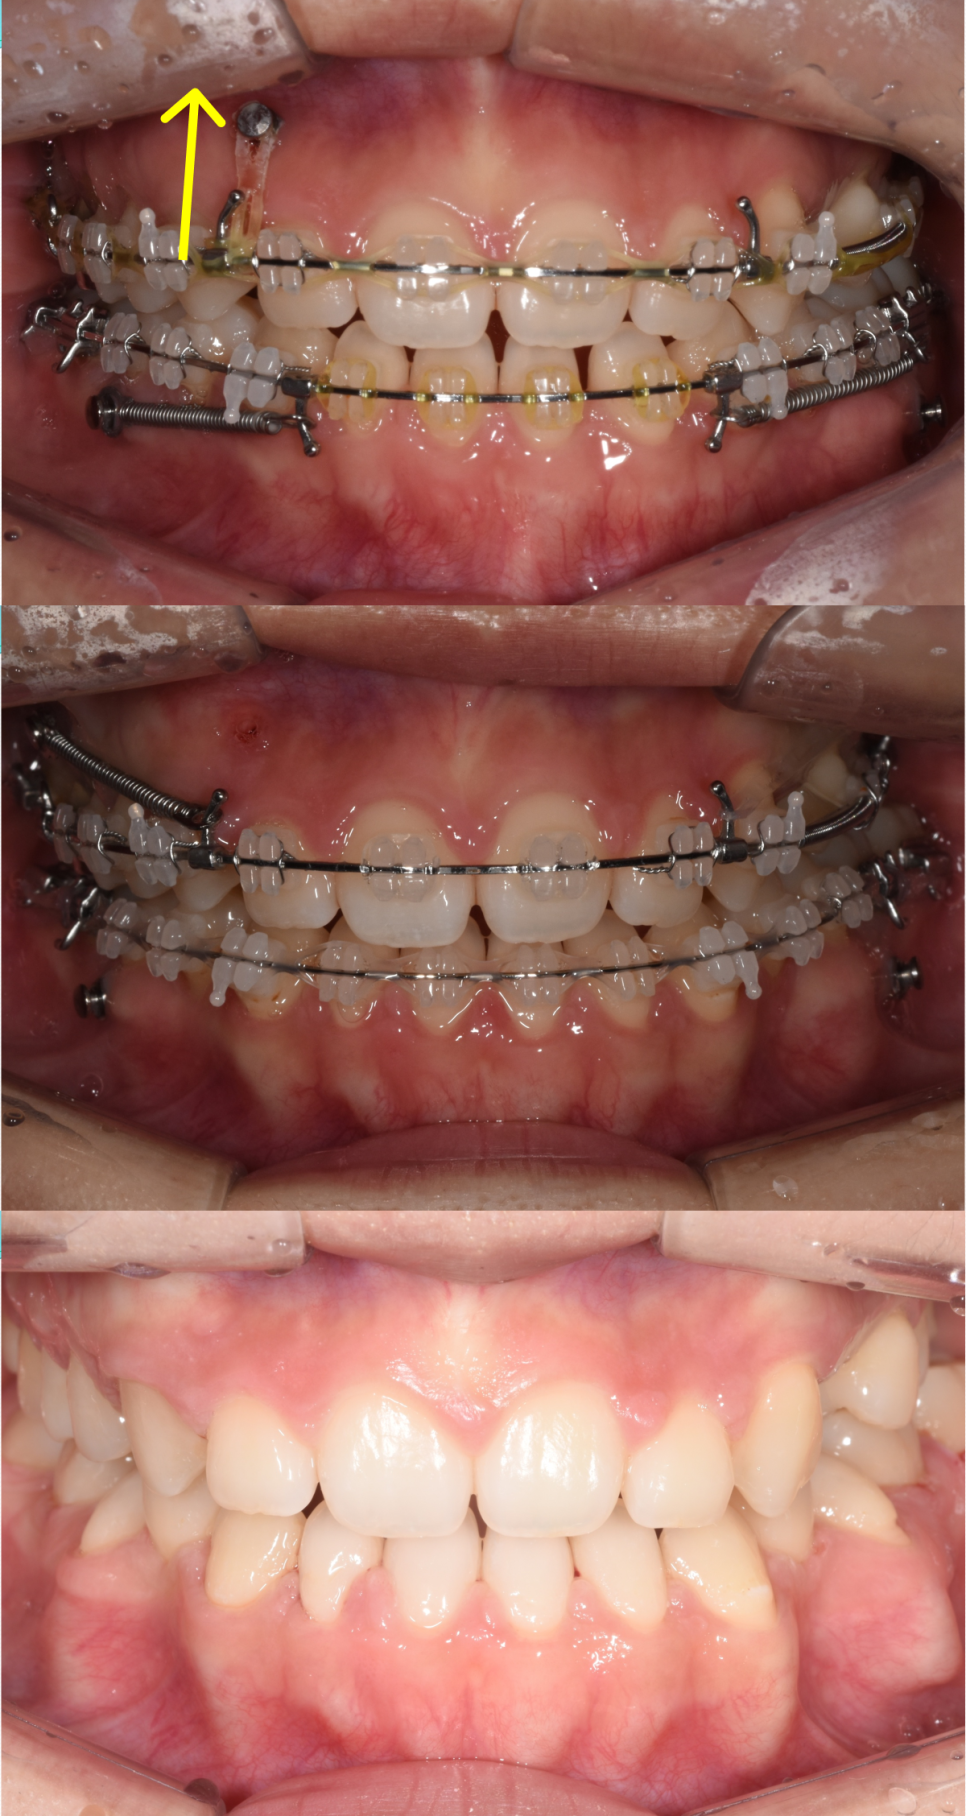

1단계: 상악 확장(위턱 넓히기)

가장 먼저 진행한 작업은 좁았던 위턱을 양옆으로 시원하게 넓혀주는 것이었습니다. 위턱이 확장되면서 아래턱과의 너비 균형이 맞기 시작합니다. 전후 사진을 보시면 좁았던 아치가 완만한 곡선을 그리며 넓어진 확실한 차이를 확인하실 수 있습니다.

2단계: 교합 개선(맞물림 조정)

위턱의 틀이 확보된 후에는 위아래 어금니가 올바르게 물리도록 세밀하게 조정합니다. 사실 이 단계까지만으로도 많은 변화가 일어납니다. 혀가 제 자리를 찾으면서 밀려 나갔던 앞니 공간이 상당 부분 개선되고, 비정상적으로 높게 물리던 교합이 안정되면서 육안으로 보이는 턱의 길이도 훨씬 짧아 보이게 됩니다.

3단계: 치아 배열 및 비대칭 정밀 조절

마지막으로 확보된 공간을 활용해 앞니를 정확한 위치에 배치하며 마무리합니다. 이때 안면 비대칭을 해소하기 위한 저만의 '히든카드'를 사용했는데요. 뼈의 길이가 더 길었던 오른쪽 부위에 미니 스크류를 식립하여 윗니를 잇몸 쪽으로 약간 압입(intrude)시켰습니다.

윗니가 살짝 위로 이동하면 오른쪽 턱이 이전보다 조금 더 깊게 물리게 됩니다. 결과적으로 길어 보였던 우측 턱이 짧아 보이는 시각적 효과가 생기면서 전체적인 안면 비대칭이 조금 더 개선되는 것이지요